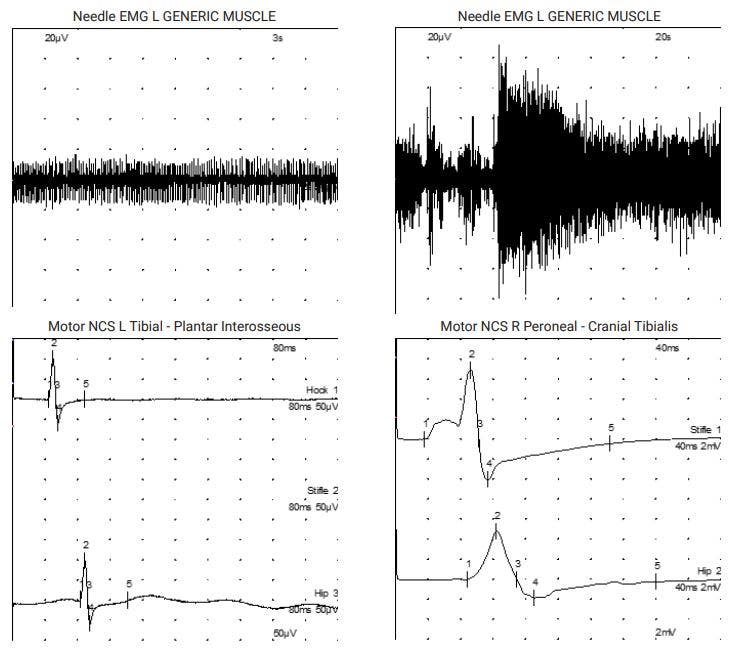

This led to referral to Thomas Mignan – specialist neurologist at Dovecote Veterinary Hospital. Thomas found the pelvic limb withdrawal reflexes decreased and absent patellar reflexes, therefore confirming our suspicion of a neuro-muscular condition. Electrophysiological testing revealed myotonic discharges and complex repetitive discharges in several muscles throughout both the pelvic and the thoracic limbs. Motor nerve conduction studies revealed markedly reduced compound muscle action potentials of the sciatic nerve but also ulnar nerve, altogether suggesting a peripheral neuropathy. Nicolas Granger was then invited to help with performing peripheral nerve biopsies. Muscle biopsies were consistent with denervation atrophy and the peroneal nerve biopsy (analysed through a collaboration with the Royal Veterinary College) revealed marked axonal loss and degeneration, with numerous axonal sprouts attempting but failing to regenerate and resulting in an axonal neuropathy.

The presence of myotonic discharges on EMG was uncommon for us and is a feature of Cushing’s myopathy, but can occur sporadically alongside other neuro-muscular conditions. Thanks to Emma’s testing, metabolic and endocrine causes for this neuropathy were ruled out.